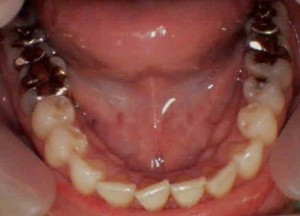

奥歯に多くの虫歯を認めます

-